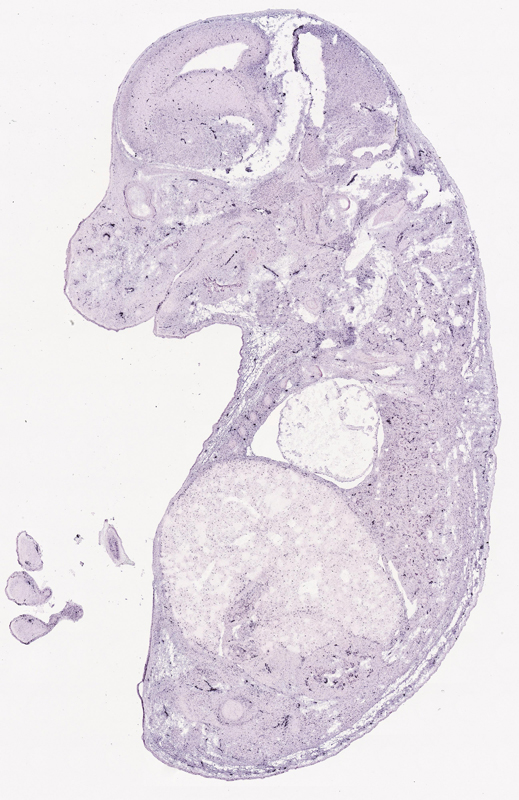

Specimen euxassay_007429_06: embryonic day 14.5 (more )

TS23: metanephros Moderate Regionally restricted euxassay_007429_07

TS23: metanephros Moderate Regionally restricted euxassay_007429_08

TS23: metanephros Moderate Regionally restricted euxassay_007429_09

TS23: metanephros Moderate Regionally restricted euxassay_007429_10

TS23: metanephros Moderate Regionally restricted euxassay_007429_18

TS23: metanephros Moderate Regionally restricted euxassay_007429_19

TS23: metanephros Moderate Regionally restricted euxassay_007429_20

TS23: metanephros Moderate Regionally restricted euxassay_007429_21